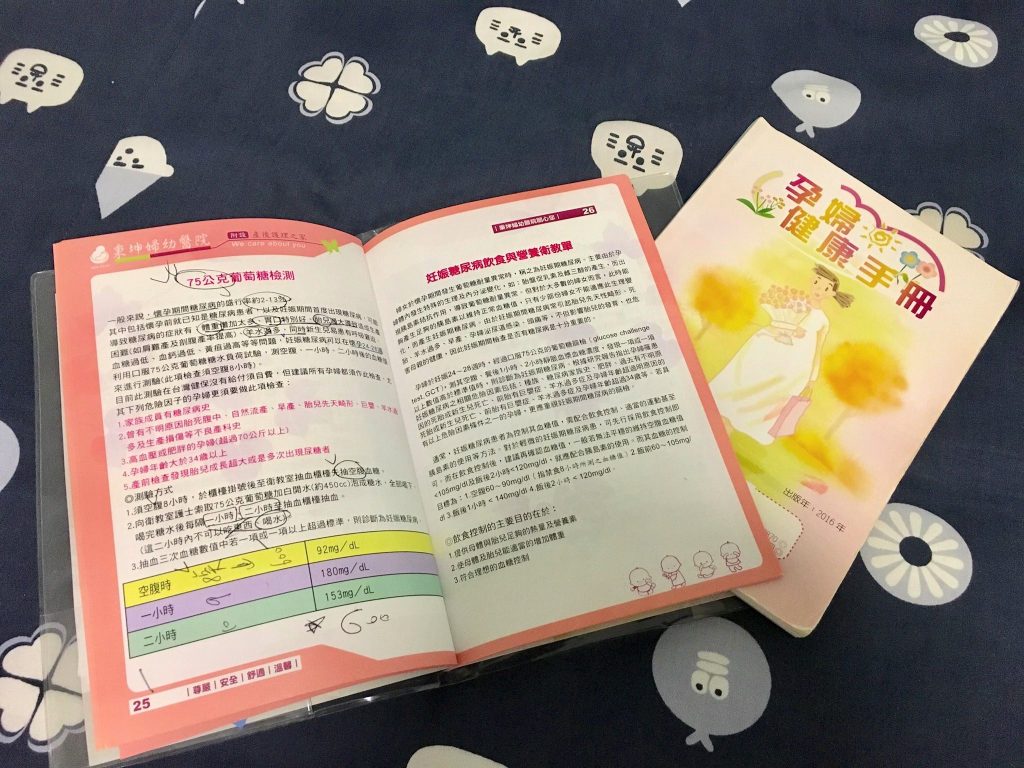

妊娠糖尿篩檢,俗稱的喝糖水,是為了檢測孕媽咪們有沒有罹患妊娠糖尿的危機,因為高糖尿會影響母體(流產、高血壓、早產),更是會危害到胎兒的健康(巨嬰、腦部發育不良、新生兒黃疸),因此這項檢測成為孕期必定檢測項目之一,建議檢查週數會落在24-28週之間。由於前一胎的甜膩膩的陰影還在,做了不少心理建設,就這樣還是在孕期第25+6週,迎來這項檢查啊~冷笑….

此項檢測需要空腹八小時,建議各位孕媽咪們可以一大早就去醫院報到,避免餓太久XD!!。而喝糖水每家醫院的流程不太一樣,鴨肉太太產檢的醫院的基礎流程是:空腹(8小時)抽一次,喝完糖水後第一個小時抽一次,喝完糖水後第二個小時抽一次,總共抽三次。由於鴨肉太太想把假用於懷孕後期再請,所以選擇下班後再去婦產科報到啊~這就是先苦後樂的概念嗎?不過,建議不要輕易嘗試,因為真的好餓啊~~~